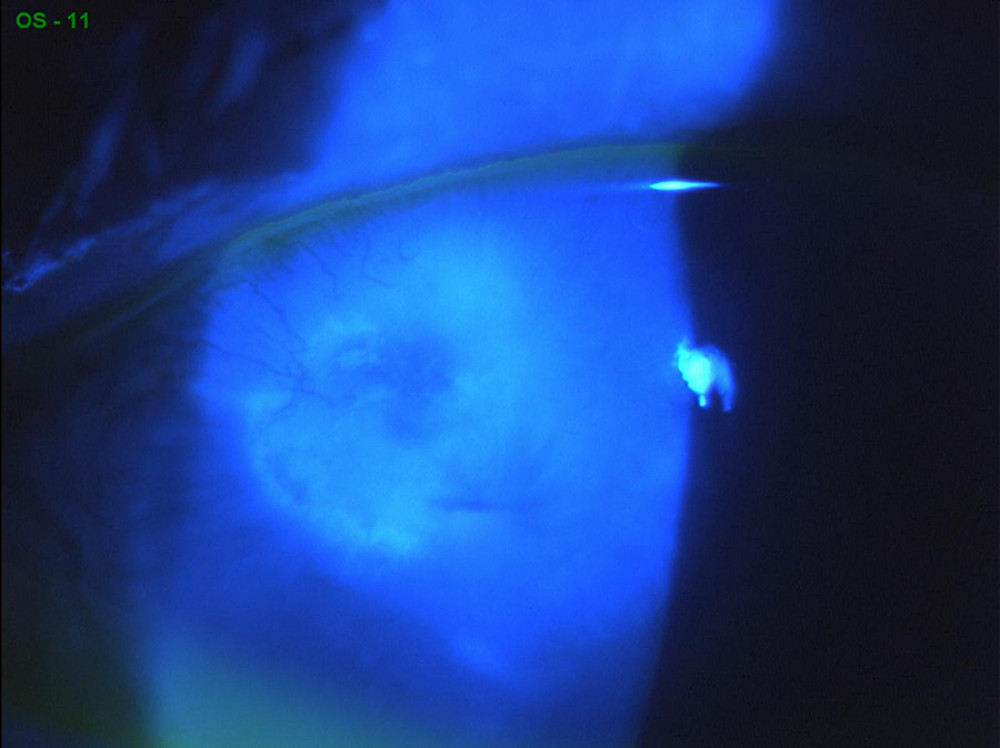

From webeye.ophth.uiowa.edu

Atlas Entry Peripheral ulcerative keratitis (PUK) in rheumatoid arthritis Rheumatoid Arthritis Eye Ulcers If a patient has an uncontrolled systemic disease such as rheumatoid arthritis, or they come off their systemic treatment for one reason or another, they can develop flares that include ocular inflammation and puk. Ra is the most common underlying condition associated with. Ocular involvement can range from. To report a case of a patient with rheumatoid arthritis (ra) and. Rheumatoid Arthritis Eye Ulcers.

Rheumatoid Arthritis Eye Ulcers . Ra is the most common underlying condition associated with. If a patient has an uncontrolled systemic disease such as rheumatoid arthritis, or they come off their systemic treatment for one reason or another, they can develop flares that include ocular inflammation and puk. Peripheral ulcerative keratitis presents with a crescent shaped destructive lesion of the juxtalimbal corneal stroma. Ocular involvement in rheumatoid arthritis (ra) can arise independently of articular and extraarticular disease 1. Ocular involvement can range from. To report a case of a patient with rheumatoid arthritis (ra) and associated peripheral corneal ulceration.

Ocular involvement can range from. Ra is the most common underlying condition associated with. Ocular involvement in rheumatoid arthritis (ra) can arise independently of articular and extraarticular disease 1. If a patient has an uncontrolled systemic disease such as rheumatoid arthritis, or they come off their systemic treatment for one reason or another, they can develop flares that include ocular inflammation and puk. Peripheral ulcerative keratitis presents with a crescent shaped destructive lesion of the juxtalimbal corneal stroma. To report a case of a patient with rheumatoid arthritis (ra) and associated peripheral corneal ulceration.